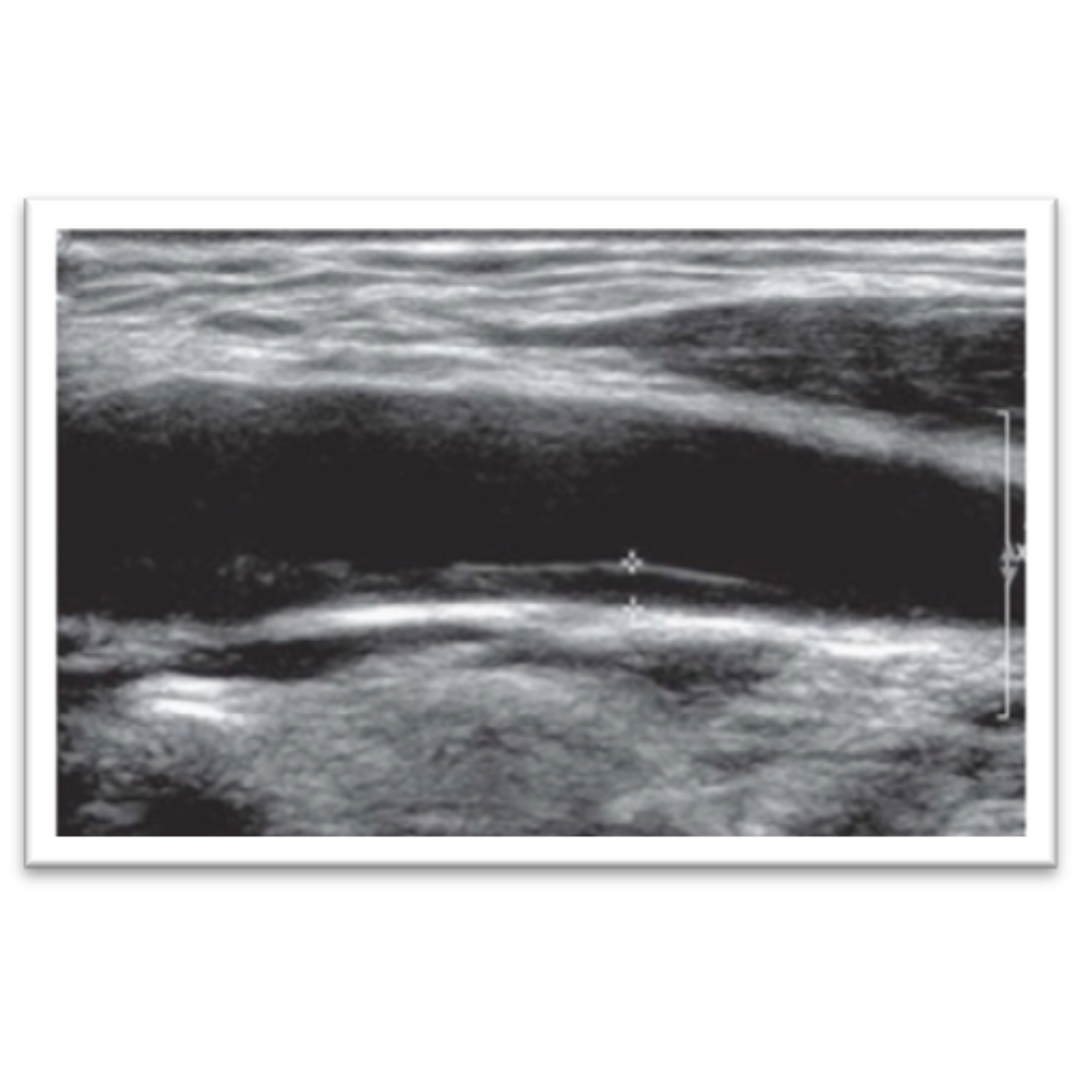

magen 2: Valoración del grosor intima-media de la arteria carótida común. Un grosor de 1 mm es considerado dentro de lo normal, mayor a 1,5 mm se considera placa de ateroma.